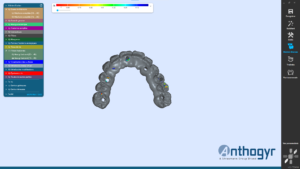

2 guides SMOP ont été imprimé, appuis dentaires, muqueux + fixation par clavettes.

Juste après la pose des implants, prise d’empreinte numérique à l’aide des transferts digitaux.

Le guide SMOP est numérisé en place avec les transferts, cela nous permet de retrouver l’occlusion.